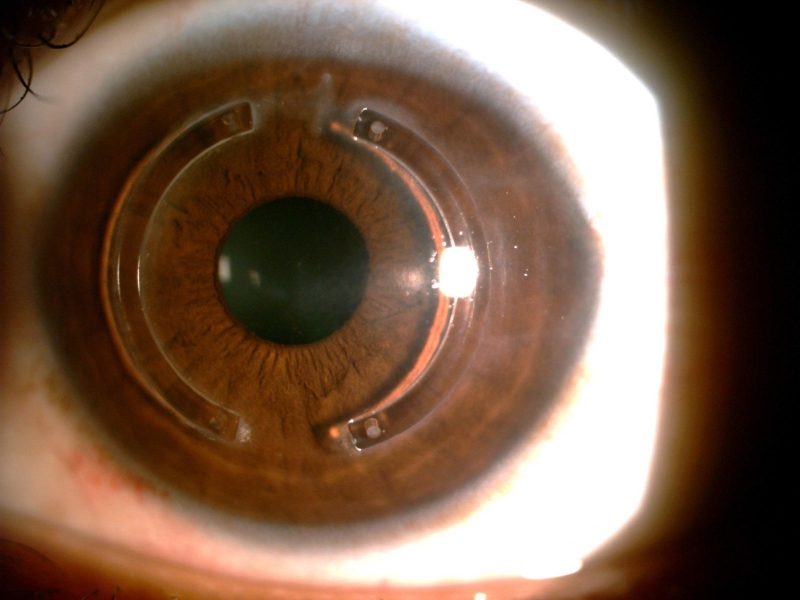

INTACS hay được dùng để điều trị cận thị độ nhẹ. Chúng là những phân đoạn hình vòng mỏng được cấy vào giác mạc, làm thay đổi đường cong của giác mạc và cải thiện thị lực. INTACS thường dùng để điều trị cận thị nhẹ hoặc loạn thị nhẹ.

/https://cms-prod.s3-sgn09.fptcloud.com/nhung_dieu_can_biet_ve_phau_thuat_mat_can_4_dbbc0f5ec5.jpeg) INTACS sử dụng trong điều trị mắt cận

INTACS sử dụng trong điều trị mắt cậnPhẫu thuật này được sử dụng để điều chỉnh cận thị nhẹ. Các vết cắt nhỏ trên giác mạc được thực hiện bằng dao mổ kim cương. Các vết cắt sẽ làm phẳng trung tâm của giác mạc và làm thay đổi đường của nó. Tương tự như PRK, vết cắt sẽ cần vài tuần để lành thương. Phẫu thuật này từng rất phổ biến, nhưng đang dần được thay thế bởi phẫu thuật LASIK.